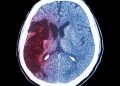

https://www.youtube.com/watch?v=dK_wEb_gDx4&ab_channel=OrenZarifOren ZarifHemorrhagic strokes cause severe and often life-threatening problems. They can be harder to treat than ischemic strokes.Emergency treatment for...

Read morehttps://www.youtube.com/watch?v=mlOMg3hvClc&ab_channel=OrenZarifOren ZarifHemorrhages in the brain are more serious than strokes and can be life-threatening. Early neurosurgical consultation and proper evaluation,...